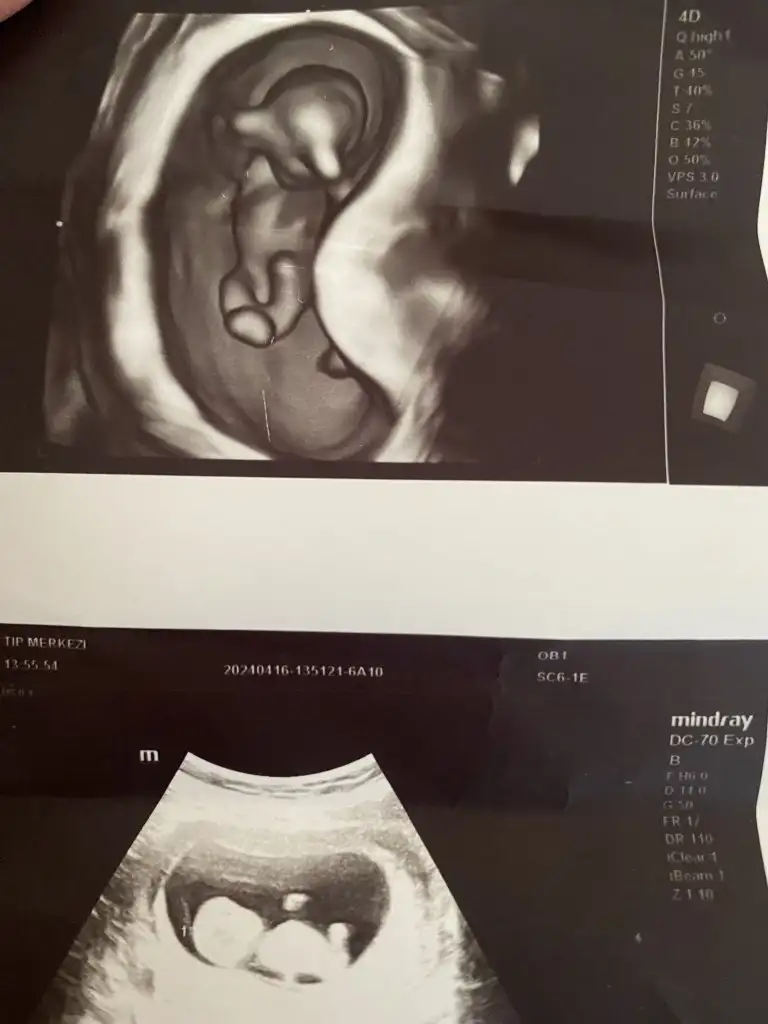

Merhaba canım sen erkek demiştin bugün doktora gittim oda erkeğe benzetti ama bilemiyorum ya tam net söylemiyor bu da yeni çekilen ultrason fotoğrafı ne diyorsun hala erkek mi

Bu da benimki 14+4 olduk bir bakın kızlar sizce ne doktor belli değil dedi henüz. Bir başka doktor da erkek gibi duruyor dedi bilemedik valaKızlar bebişlerinizin ultrason resimlerini ve cinsiyetini kaçıncı haftada olduklarını yazında kendi ultrason resimlerimizle kıyaslayıp fikirde bulunalım. Nub teorisi, kafa şekli, kemik yapısından cinsiyet teorileri tutuyor mu bakalım bir![]()